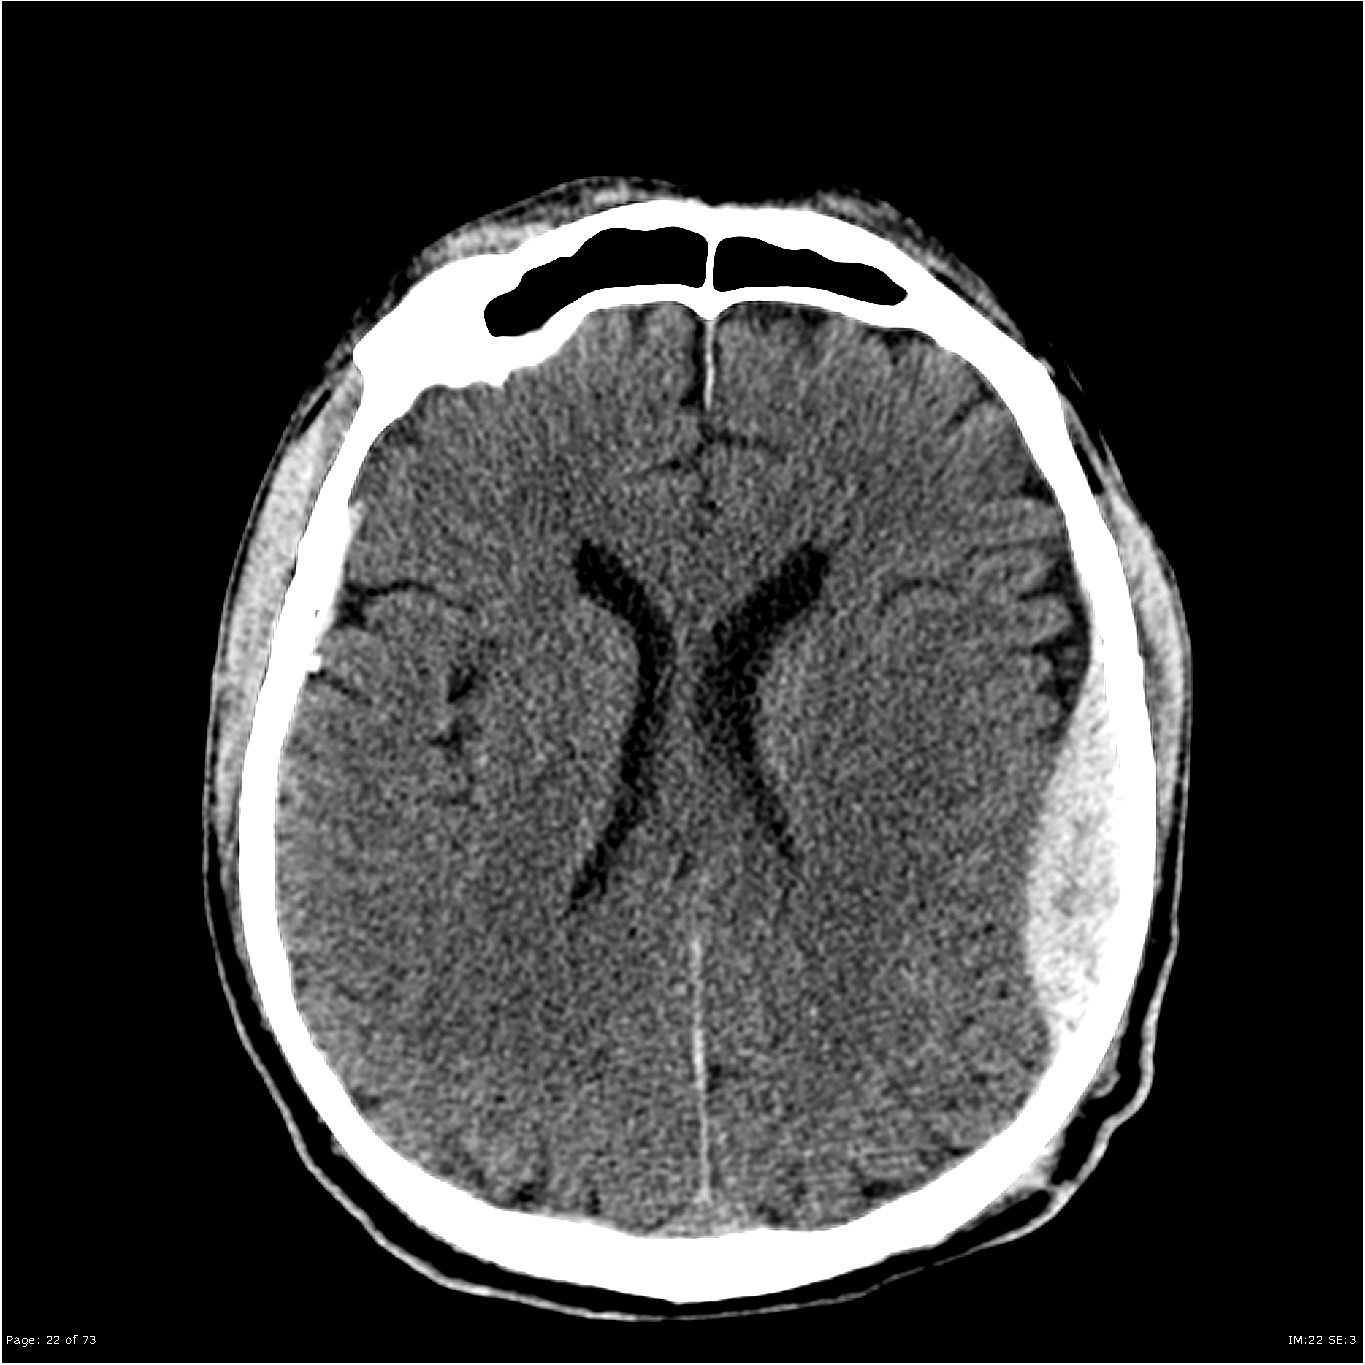

Consultant Radiologist Nick Carter joins us again to take us through interpretation of the head CT in the context of trauma. Starting with typical injuries and the patterns they show, features to aid pattern recognition and the key features on images that help guide and empower us to make the early referral to neurosurgery.

Images courtesy of Dr Derek Smith, Radiopaedia.org from the case rID: 36667, Case courtesy of Assoc Prof Frank Gaillard, Radiopaedia.org. From the case rID: 19252